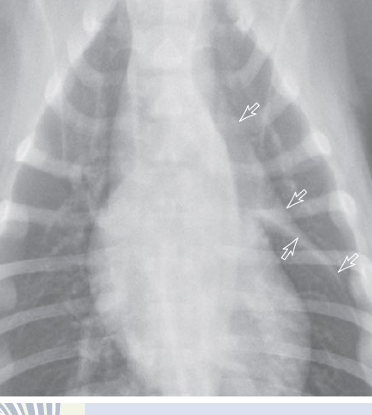

VD

arrow pointed the THYMUS

dark white: right margin of trachea

light white arrow: left margin of trachea